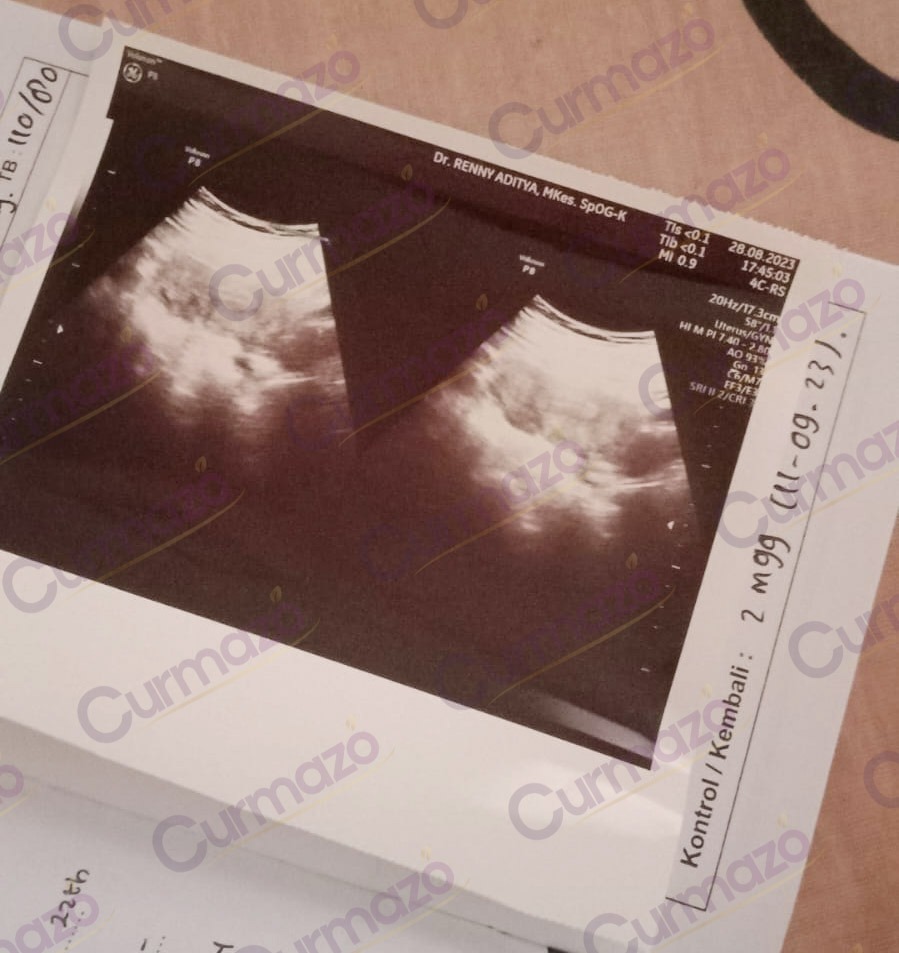

Setelah 2 bulan pengobatan herbal, saya sudah tidak merasakan nyeri di pinggang, keputihan dan haid juga sudah normal. Karena merasa sudah tidak ada keluhan, pada 28 Agustus 2023 saya periksa, hasilnya miom sudah hilang.